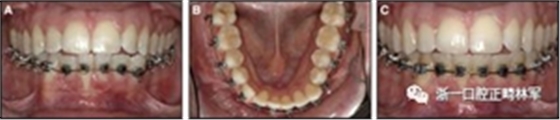

粘合保持器被移除,并放置固定裝置(圖15),僅限于患者要求的下頜弓。在第一階段牙周過(guò)程中,將結(jié)締組織移植物置于下頜右側(cè)中切牙的面?zhèn)取?個(gè)月后進(jìn)行第二階段牙周過(guò)程(圖16)。包括有意識(shí)的垂直骨質(zhì)評(píng)分以啟動(dòng)區(qū)域加速現(xiàn)象,以及顯著的面?zhèn)群蜕鄠?cè)植骨以糾正骨開(kāi)窗。

隨著時(shí)間的推移,全維度弓絲及其表達(dá)的牙齒間扭矩差異顯著改善(圖17)。明智的鄰間減少之后,間隙關(guān)閉擴(kuò)大接觸面,消除不美觀的黑三角。在脫粘之前也校正了牙齒排列和牙弓形態(tài)(圖18)。

之前和之后的三維圖像(圖19)突出顯示在下頜右側(cè)尖牙面?zhèn)缺砻嫔瞎堑脑黾右约扒把姥栏恢玫母纳啤S捎谙骂M切牙的伸長(zhǎng)被認(rèn)為是不嚴(yán)謹(jǐn)?shù)?,因此輕度前牙開(kāi)合沒(méi)有被矯正。

圖15.下頜右側(cè)中切牙區(qū)域軟組織移植前的初始排齊:A,正面視圖; B,咬合面視圖; C,軟組織移植2周后,初始牙周手術(shù)。